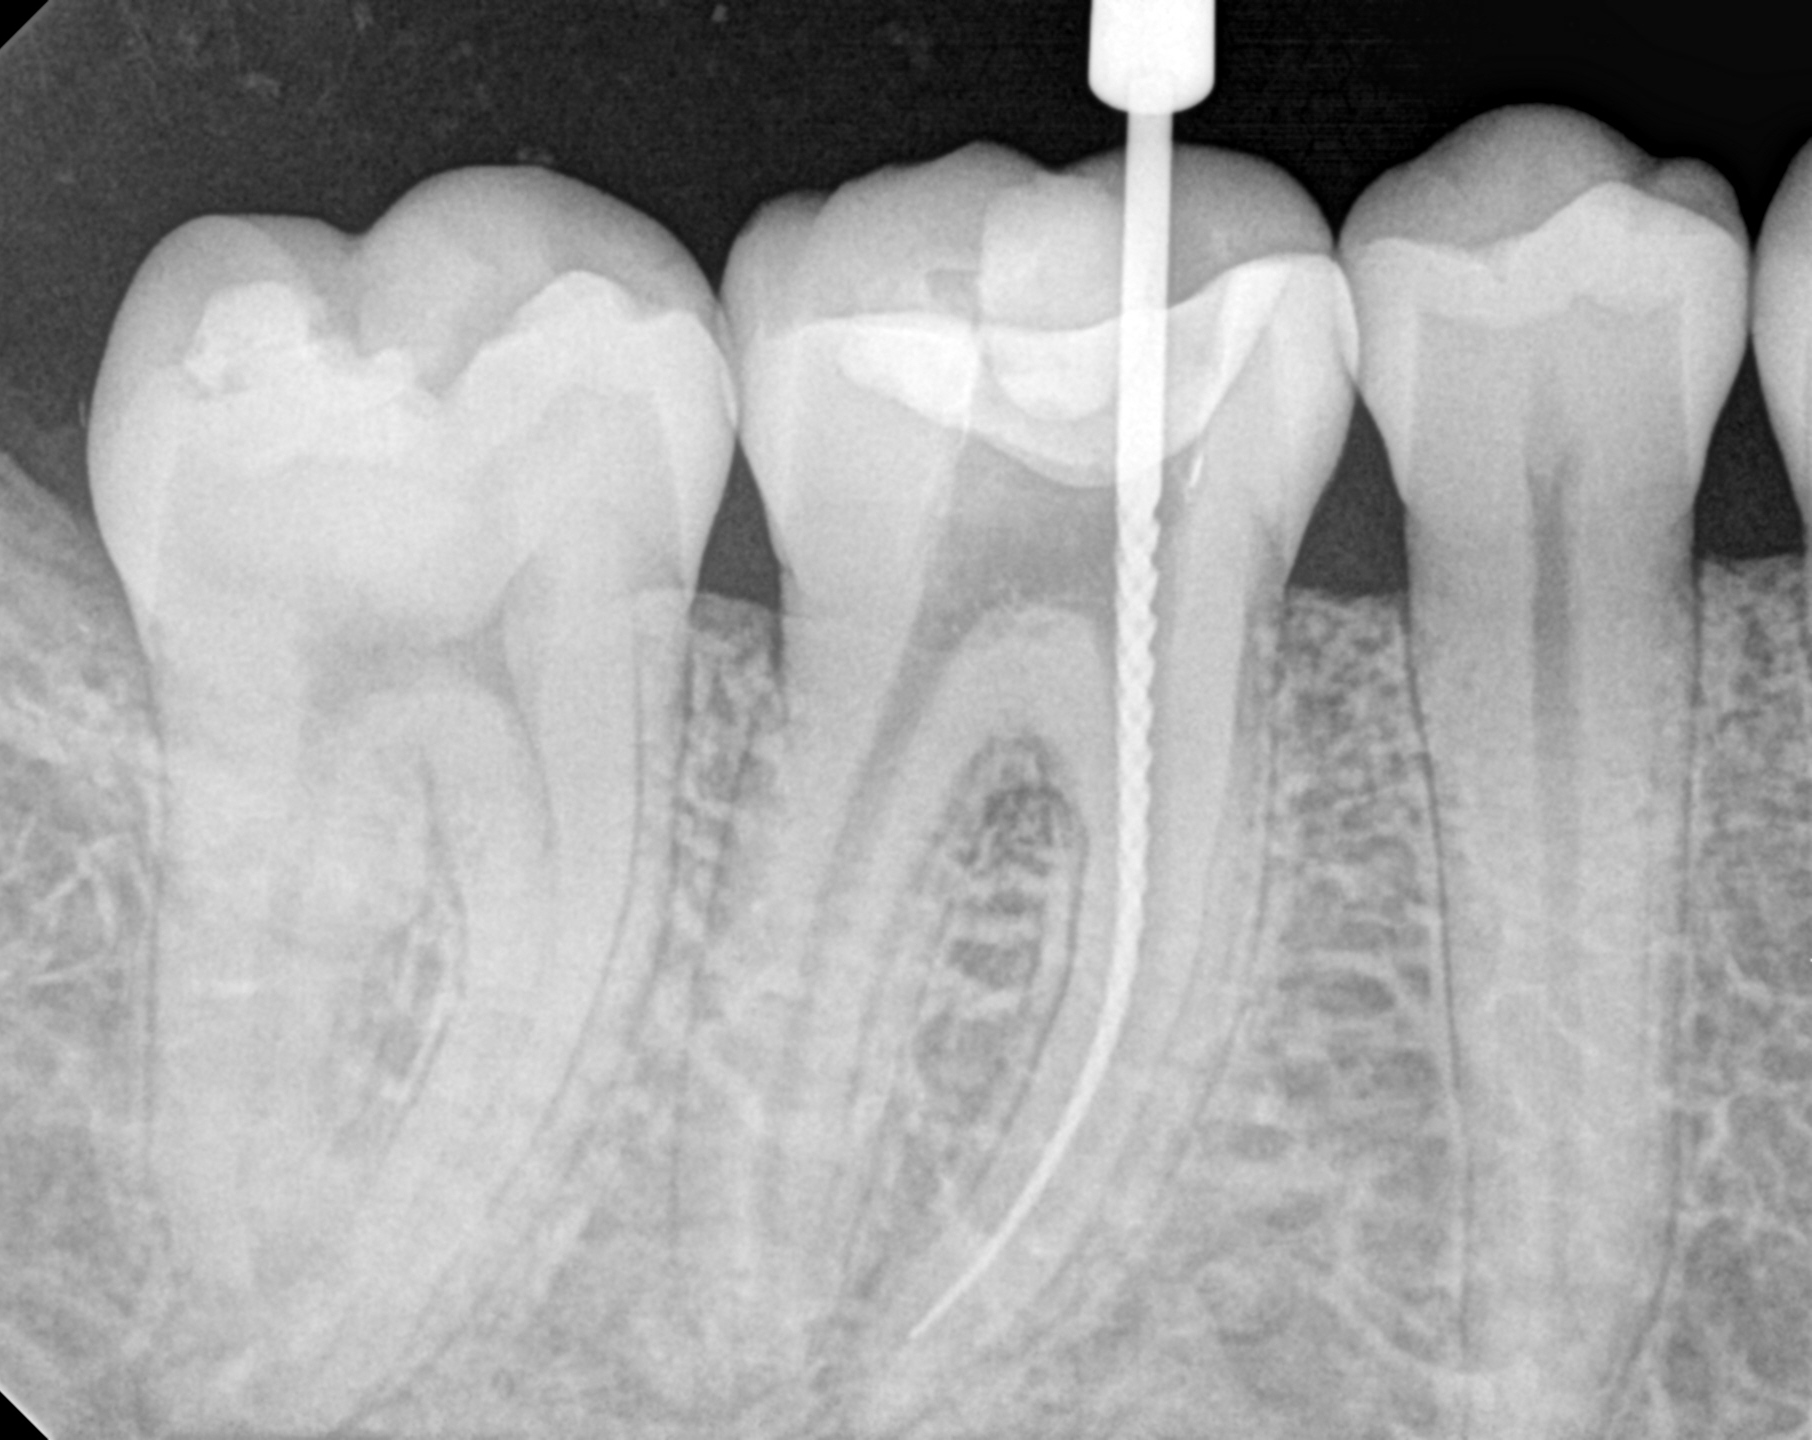

Endodontics & Root Canals

If you are suffering from a tooth infection caused by decay or injury, you may be in need of a root canal. In our Santa Monica office, we will work with you to discuss the root canal treatment and ensure that your procedure is painless and effective, leaving you with an improved, healthy smile after just one visit.

Our patients receive top-quality care for their endodontic treatment. Root canal therapy is performed when the tooth's root becomes infected due to cavities or cracks, causing discomfort and swelling in the area. The procedure involves cleaning out the root canal to prevent further damage and save your tooth. When performed by our dentist, Dr Haber, you can be sure that your smile is restored to show healthy and beautiful results.

Root canal , the pulp chamber, dental pulp, root end, apex, number of root canals per tooth depends on the number of the tooth roots ranging from one to four, five or more in some cases. Sometimes there are more than one root canal per root, variable internal anatomy. An unusual root canal shape, complex branching and multiple root canals are considered as the main causes of root canal treatment failures.,  a secondary root canal goes unnoticed by the dentist and is not cleaned and sealed, it will remain infected, causing the root canal therapy to fail. lateral parts fins, anastomoses and accessory canals, lateral component , vital or necrotic pulp, infectious elements . a single root contains two canals, mesial roots of lower molars. radiographs, cone beam computerized tomography , CBCT , rotary nickel titanium (NiTi) files ,  canals with flat-oval or tear-shaped cross sections, lingual recesses remain un-instrumented. canal is flat and use of hand instruments to try to overcome this problem, Tissue or biofilm remnants along such un-instrumented recesses may lead to failure due to both inadequate disinfection and the inability to properly obturate the root-canal space.